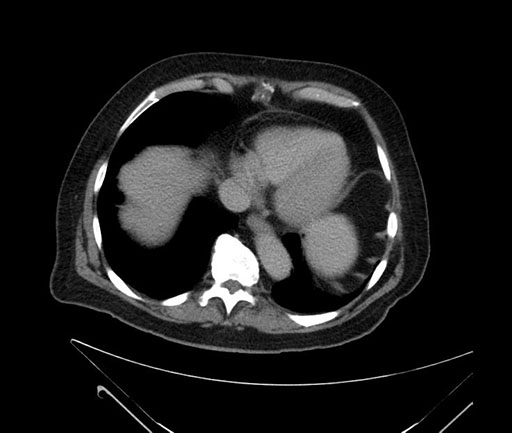

Axial - 3 months prior